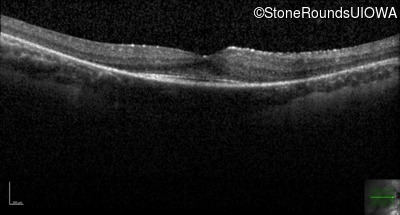

Optical Coherence Tomography - Right - 20/20 sc

Exemplar / OCT Stack

OCT Stack